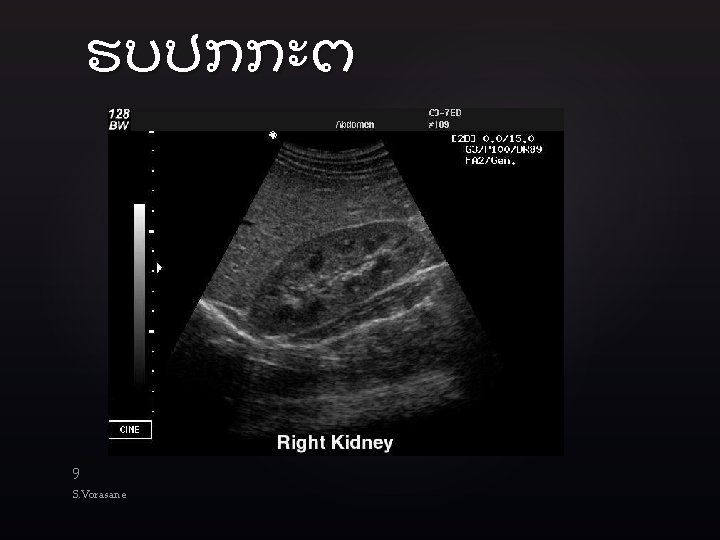

Technique l Goal: to identify blood in body cavities where it is not supposed

Technique l Goal: to identify blood in body cavities where it is not supposed to be l l Unclotted blood appears black on US Clotted blood appears gray Abdominal probe with small footprint (between 13 cm) with range of frequency between 2. 0 Hz and 5. 0 Hz Scan 4 areas l l RUQ Subxiphoid LUQ Suprapubic